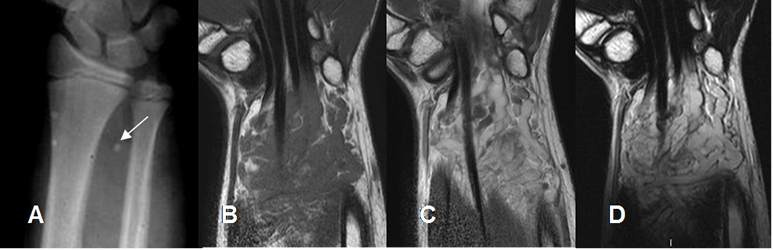

Fig 146. Hemangioma.

A: Rx AP. Prominencia de tejidos blandos en el antebrazo distal, con presencia de flebolito.

B: RM coronal en T1 simple, C: RM coronal en T1 con contraste y D: RM coronal en T2. Lesión de tejidos blandos compuesta por vasos dilatados, hipointensos en T1, hiperintensos en T2 y que realzan con el contraste, por hemangioma.